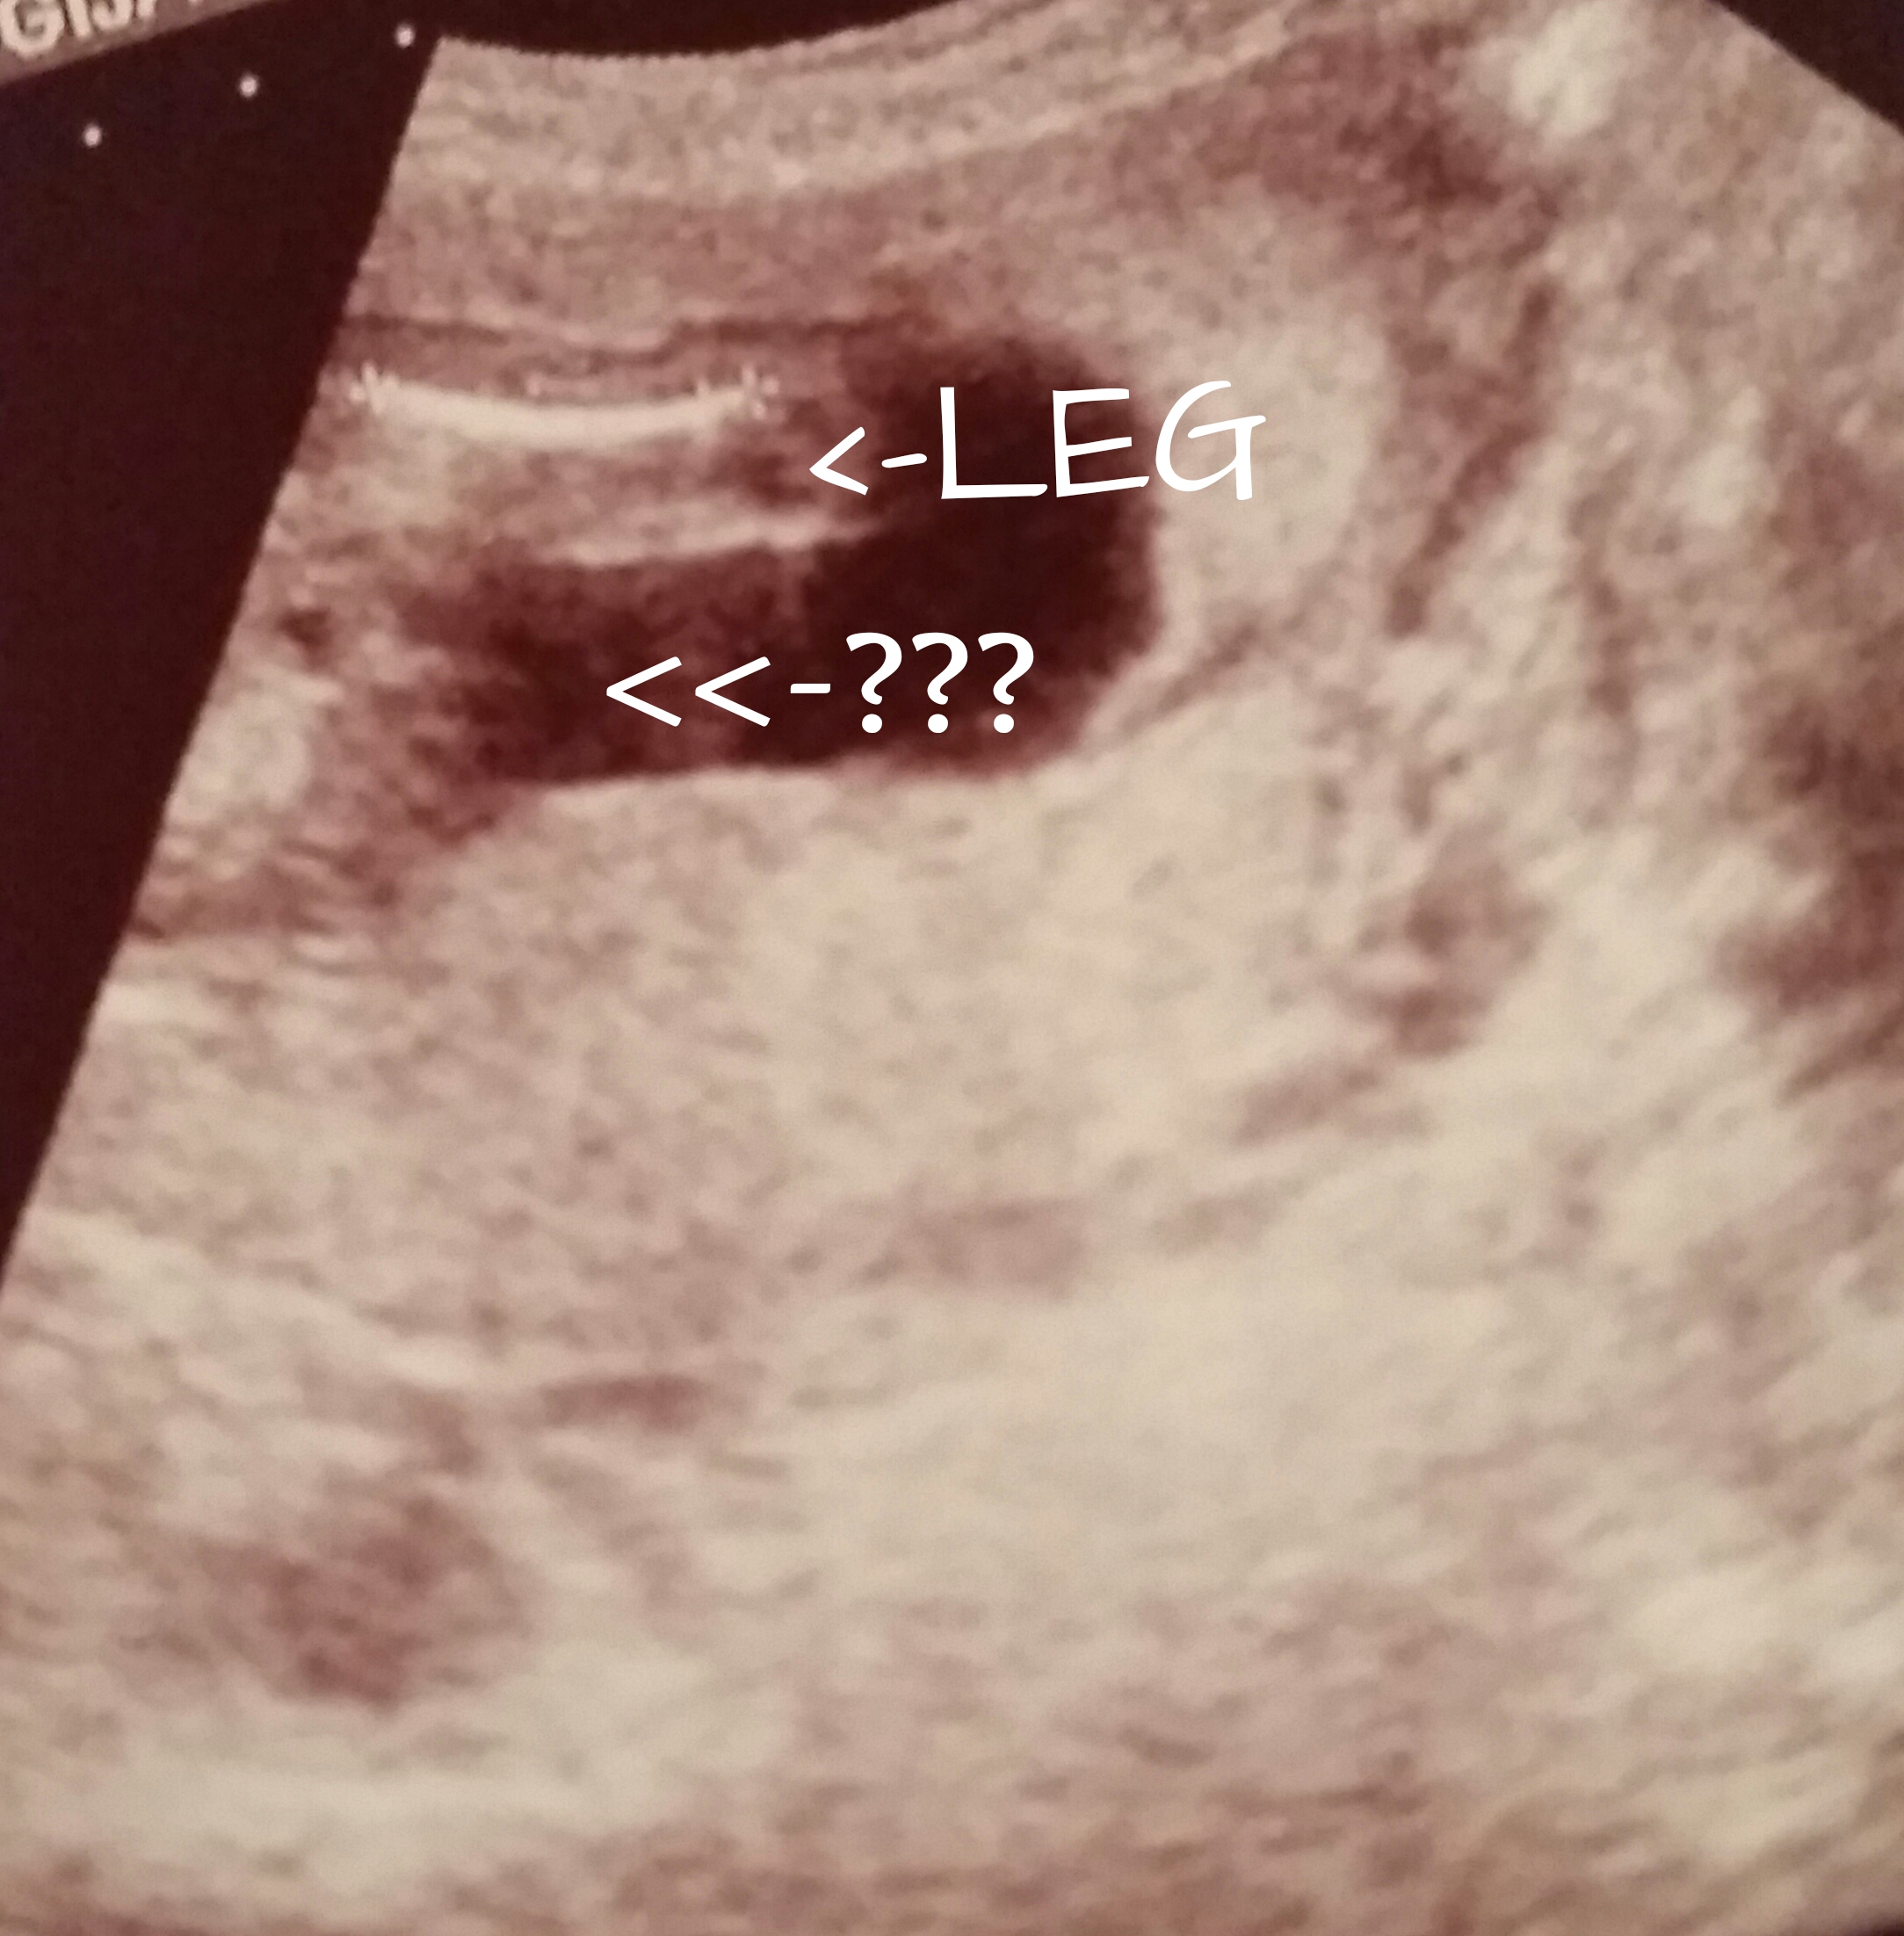

Attachment 20928 16 weeks abdominal ultrasound..

Boy

Probably boy

Not clear to me at all.